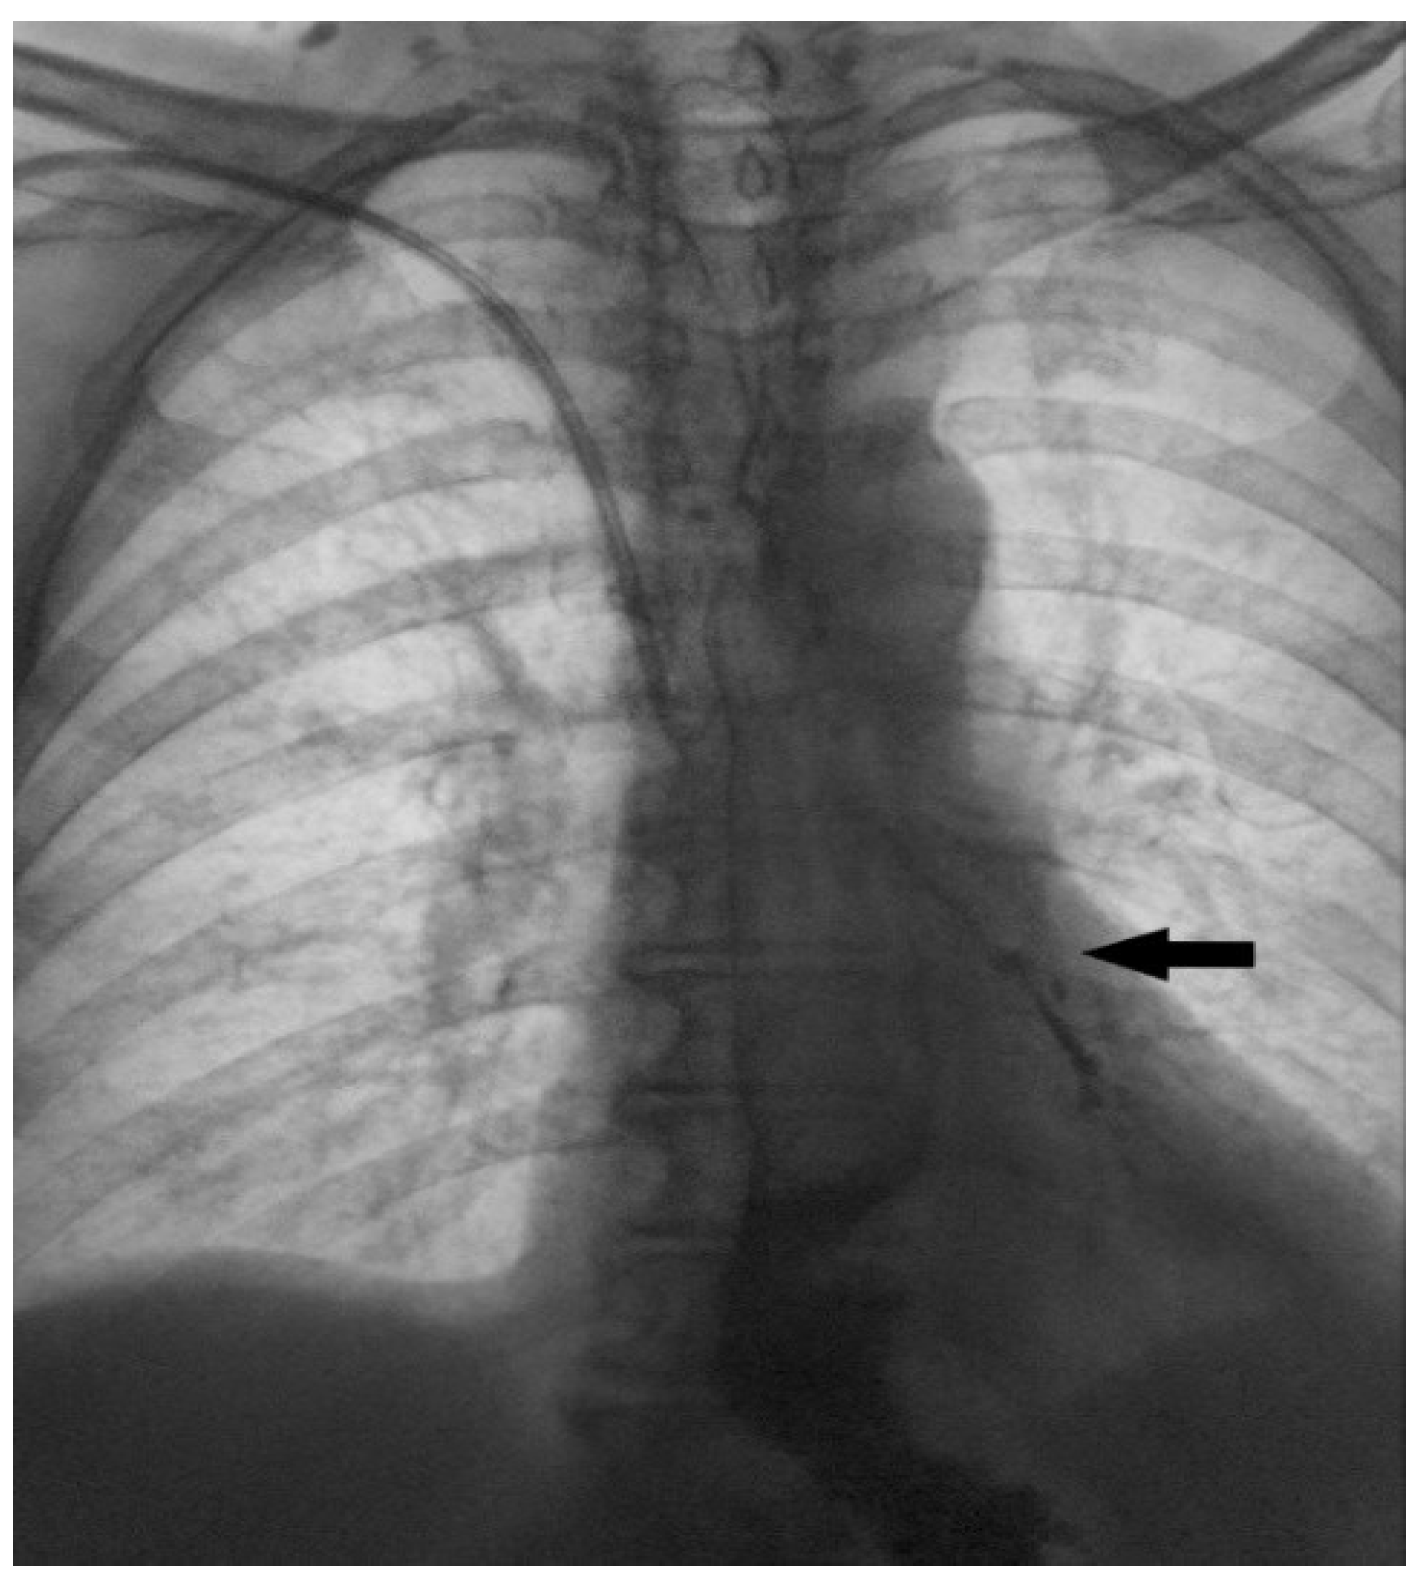

Figure 8. In order to thoroughly control and monitor the unusual procedure, all necessary diagnostic methods were performed three months after and the correct position and clear epithelialization of the fistulous tract were confirmed, first by upper GI endoscopy (a) (black arrow showing the obliterated lumen of the opening in the esophageal wall) and then by contrast X-ray examination (b), where no extraluminal gastrografin enema was observed (black arrow). An upright posteroanterior (PA) chest radiograph (c) shows the bent wire component of the coil in a correct position (red arrow), while a CT examination (d) confirms the correct localization of the coil within the fistulous tract with completely closed openings in the wall of the esophagus and trachea (red arrow). At that time, percutaneous gastrostomy was removed, and three months after a planned laparoscopic cholecystectomy was performed without intraoperative or postoperative complications. In the recent literature, off-label occluding devices have been used in treating TEF, usually cardiac septal defect occluders. These kinds of devices have been utilized in selected cases, especially in benign TEF and broncho-esophageal fistula [10]. However, its use has been associated with great airway complications, such as airway obstruction mainly due to mucus build up and granulation tissue. In some cases, a denovo fistula could arise due to the erosive effect that the device could have on the tissue [11]. Other approaches have used an Acell matrix (a decellularized porcine urinary bladder matrix), which has been used in treatment of benign TEFs due to its ability to enhance the healing process. Complete closure has been reported in some cases within 10 days [12]. Nevertheless, these approaches remain rarely used due to limited evidence and lack of validation in larger patient groups. Tissue adhesives such as fibrin and cyanoacrylate glue have represented another modality that can be utilized alone or in addition to other occluding devices [13]. The application of these adhesive glues is usually reserved for the pediatric population but has been found in the treatment of the adult population [14]. These agents show a better success in treating more proximal lesions, where the applicability of stents is limited. Having said that, greater outcomes using these agents are usually seen in smaller fistulae and could offer a safer approach in patients with contraindication for severe surgical procedures [15,16]. Endoluminal vacuum-assisted closure (EVAC) therapy has recently emerged as a potential option for TEF management. While promising, EVAC use in TEF remains largely limited to case reports and small series [17].